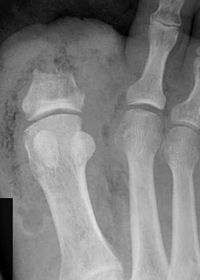

Describe what is occurring at the head of the 3rd met | Freiberg’s infarction (avascular necrosis of the metatarsal head) |